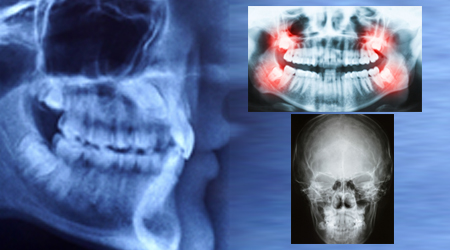

RVG (Small X-Ray) 200 5

Procedure INR US

OPG (Full Mouth X-Ray) 500 10

CT Scan 5000 80